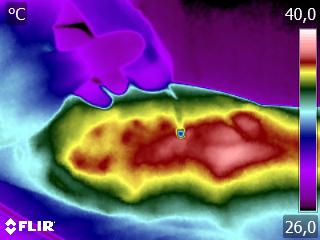

Como no caso do termograma abaixo de uma aplicação de laserterapia em antebraço direito. Esta aplicação foi realizada com a técnica Termoguiada para uma melhor precisão dos pontos de aplicação. Isso porque, como a paciente estava com muita dor e a espessura do feixe do laser é menor que 0,3 cm, deve-se ter muita precisão na aplicação da radiação laser para se promover a analgesia.

Isso potencializa os efeitos da terapêutica, pois a radiação será aplicada exatamente nos pontos de maior necessidade, não desperdiçando luz ao longo da sessão. Assim, a aplicação da laserterapia gera melhores resultados para o seu paciente e para a sua terapêutica.